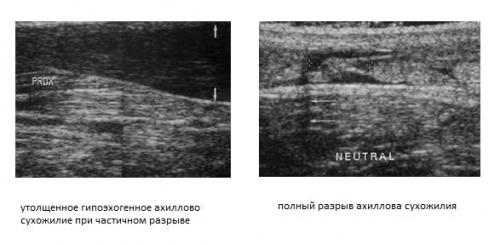

Клинический осмотр и применение диагностических тестов позволяют точно установить диагноз у 70% больных. На помощь специалисту приходят такие методы как сонография (УЗИ) и МРТ. Сонография – очень точный, быстрый, малоинвазивный и дешёвый метод диагностики разрывов ахиллова сухожилия – но только в руках опытного специалиста. Позволяет отличить частичные и полные разрывы.

Опытный специалист может быть с успехом заменён на качественное программное обеспечение и использование высокопольного МРТ.